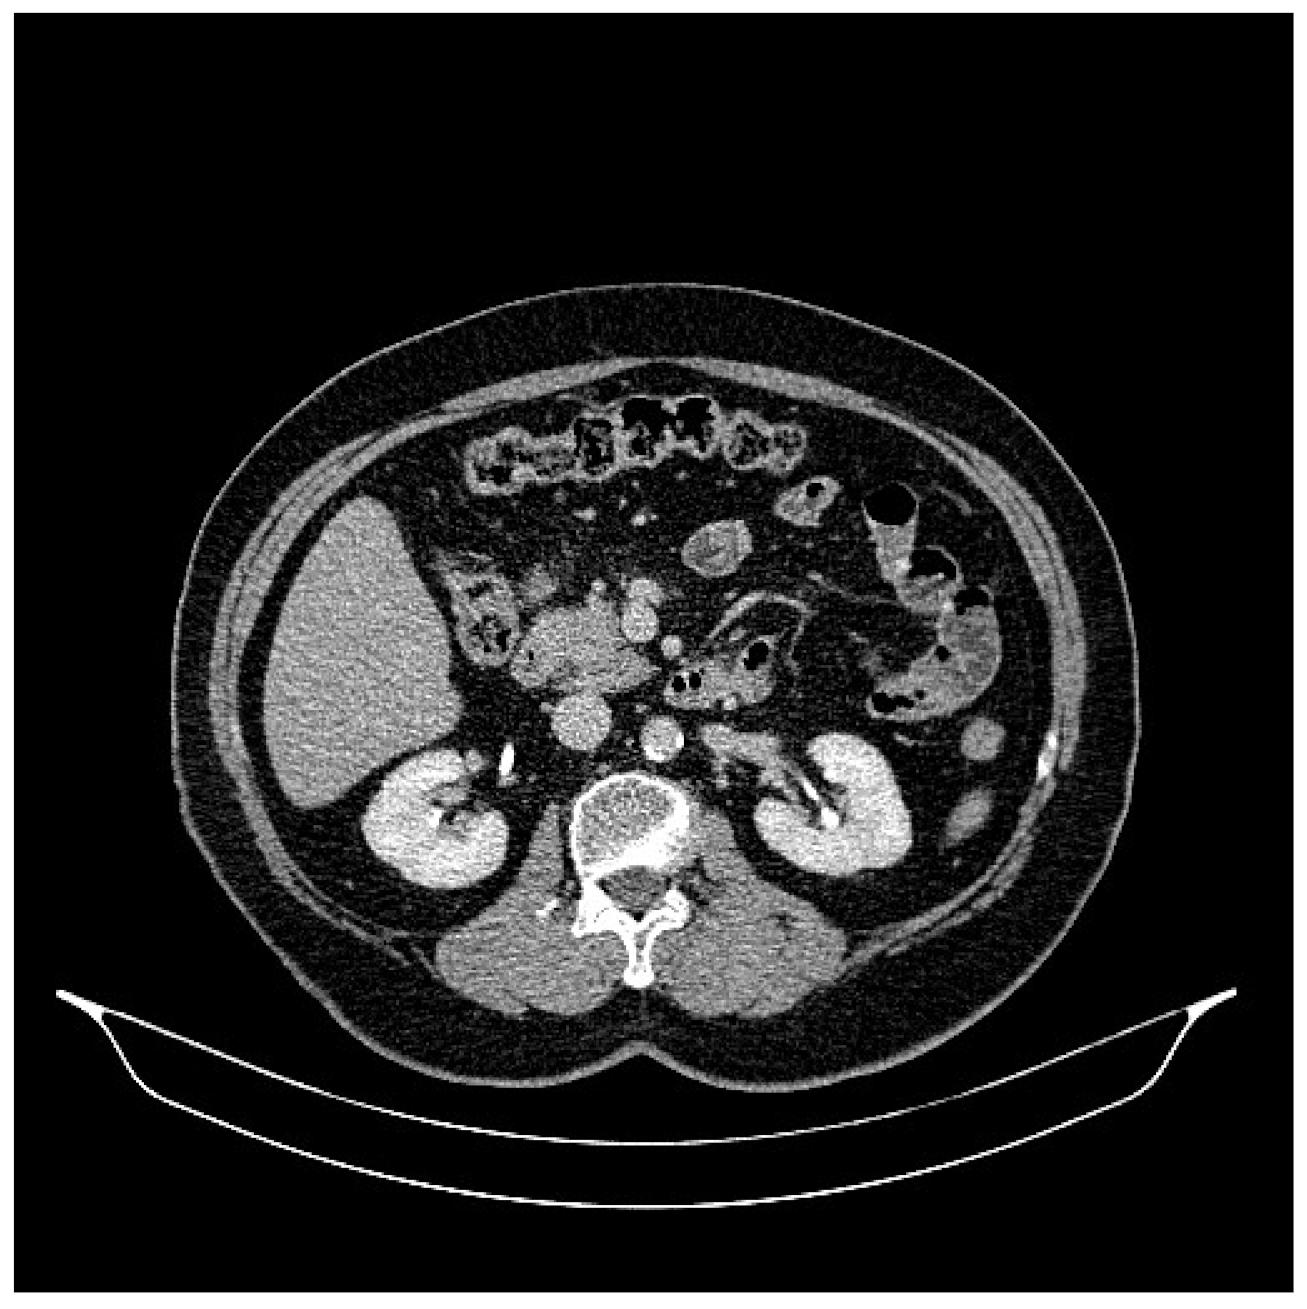

2. Case Presentation